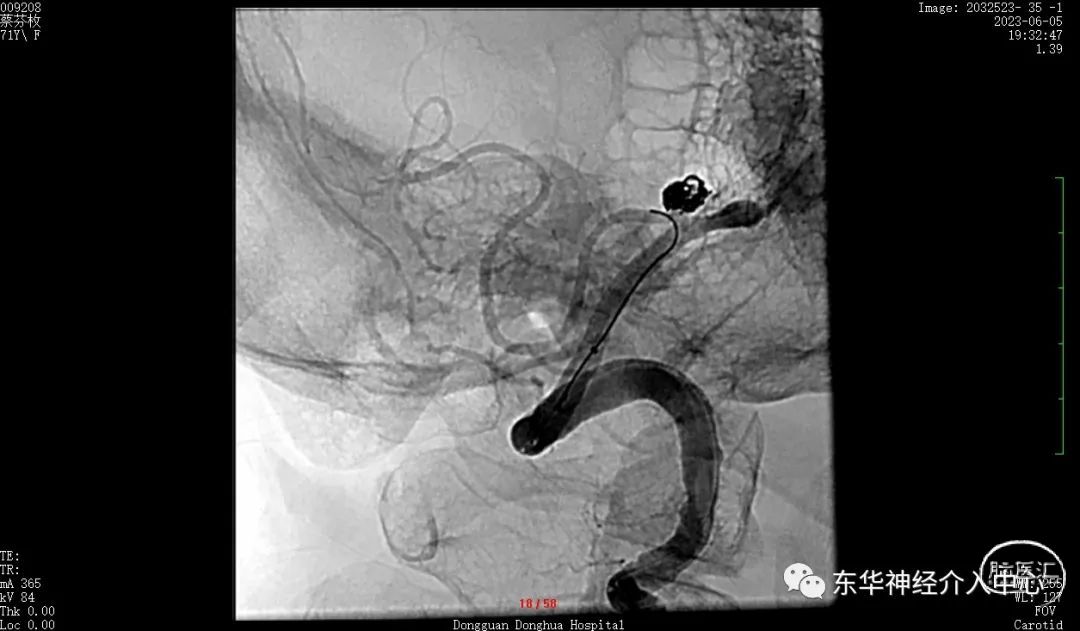

同侧椎动脉的开口狭窄,置入中间导管后血流不通畅。不得不进行开口的扩张。这倒是简单。扩张后顺利将中间导管置入合适位置。开始进行真正的动脉瘤栓塞术。

但是换用了三种微导丝都是难以将微导丝进入到PICA 的远端。考虑可能是动脉瘤稍远的PICA 内有斑块阻挡。微导丝不能到达远端,支架导管就不能进入其内,采取支架辅助栓塞动脉瘤已经不现实了。但是手术不可能放弃呀。曾经也拜读过有同道的文章采取微导丝来辅助栓塞动脉瘤、只能尝试一下了,但是风险更大、难度更高。不过令人欣慰的是经过反复的调整,第一个成篮圈非常满意。

如此信心大增。继续填塞。终于满意的将动脉瘤栓塞,动脉瘤完全不显影。